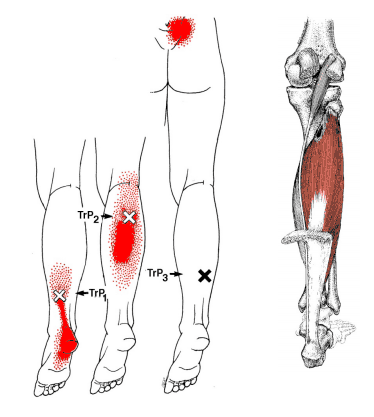

3.ヒラメ筋による肩甲骨まわりの張り・腕の痛み

ヒラメ筋は、ふくらはぎの深い位置にある筋肉で、立っている姿勢を支えたり、歩く際に足首を安定させる働きを持っています。

このヒラメ筋に トリガーポイント(×印の部分) ができて固まると、坐骨神経痛と似た症状が脚全体に広がることがあります。

主な症状としては、

- ふくらはぎの奥の痛みや張り感

- お尻に響くような放散痛

- 足裏(特にかかと付近)の鋭い痛みやしびれ

などが挙げられます。

赤い範囲のように、ふくらはぎ〜足裏にかけて痛みが広がるのが特徴で、「歩き始めに足裏が痛い」「ふくらはぎがずっと張っている」という方によく見られます。

ヒラメ筋が硬くなると、下肢全体の血流が悪くなり、坐骨神経痛の症状をさらに強めることがあるため、早めのケアがとても重要です。